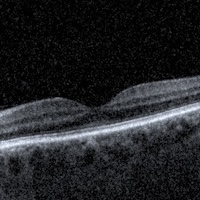

Optyczna Koherentna Tomografia (OCT) to jedno z najnowocześniejszych badań diagnostycznych dostępnych w okulistyce i optometrii. Umożliwia ono niezwykle dokładne obrazowanie struktur oka w technologii 3D, z rozdzielczością pozwalającą zobaczyć nawet najmniejsze zmiany w siatkówce czy nerwie wzrokowym. OCT można porównać do swoistego „rezonansu oka” – bezbolesnego, szybkiego i całkowicie nieinwazyjnego.

OCT pozwala na wczesne wykrycie wielu chorób oczu, zanim jeszcze pojawią się ich pierwsze objawy. Dzięki temu badaniu można precyzyjnie ocenić:

• stan siatkówki i plamki żółtej,

• grubość i strukturę włókien nerwu wzrokowego,

• obecność zmian zwyrodnieniowych, obrzęków czy uszkodzeń.

Badanie trwa zaledwie kilka minut. Pacjent siada wygodnie przed urządzeniem przypominającym aparat fotograficzny, wpatrując się w punkt świetlny. Specjalistyczna wiązka światła skanuje oko, tworząc przekroje i obrazy poszczególnych warstw siatkówki. Warto podkreślić, że nie ma żadnego kontaktu urządzenia z okiem, nie trzeba stosować kropli znieczulających, a cały proces jest całkowicie komfortowy i bezpieczny.

Tomograficzne badanie wzroku z wykorzystaniem nowoczesnego sprzętu diagnostycznego w celu oceny przedniego lub tylnego odcinka oka. Badanie zostaje ocenione przez lekarza specjalistę okulistyki. Wynik badania otrzymujesz w formie wydruku.